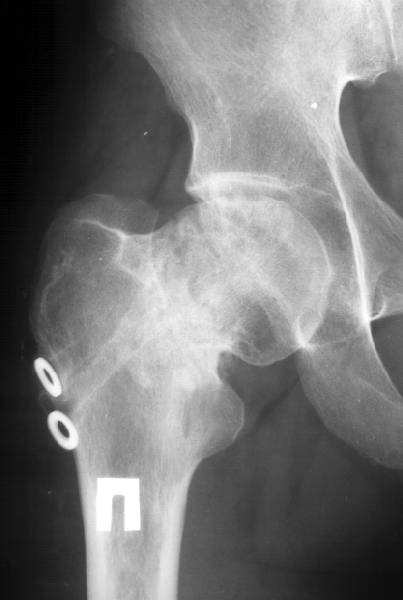

A male (32 y.o, 175 cm, 65 kg) after a car accident 1 year ago sustained a femoral neck fracture. The fracture was fixed elsewhere by cancellous screws. He noted telescoping of the screws four month later. Recently the screws have been removed. Walks with cane and marks hip pain. Xrays and CT (see attachment) demonstrate pseudarthrosis of the neck.

In a 32 year old male with a femoral neck nonunion, his best option is probably a valgus producing intertrochanteric osteotomy with blade plate fixation. In the preoperative planning stage, neutral rotation (patella up) 100% films of both hips are necessary. The AP film enclosed is with significant external rotation given the appearance of the lesser trochanter. It doesn't appear that there is significant retroversion based on the CT scan. Depending upon what his neck shaft angle is compared with his normal side, a better recommendation of the degree of osteotomy can be made. Predictable results (ie union) can be obtained without trying to reproduce a fracture angle of 25 degrees. That is, a 20 or 30 degree valgus producing intertrochanteric osteotomy with a 110 degree or 120 degree blade plate, respectively, should give a reliable result. According to the preoperartive plan with comparison to the contralateral hip in the same rotation, the lateralization of the shaft can be accomplished to help minimize proximal deformity and lateral compartment overload of the knee (theoretically). Length can be simultaneously gained as well.